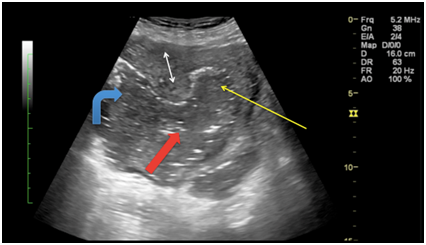

Non-contrast CT scan of pelvis (Figure 2A) confirmed the defect in right lateral wall of uterus (thick red arrow) with multiple loculated air containing collections in right adnexa (curved blue arrow) and endometrial cavity (thin yellow arrow). Right adnexa showed heterogeneous solid appearing mass with presumably fetal parts including head (red circle in Figure 2B).

Figure 2 Non-contrast CT scan of pelvis; Figure 2A revealed the defect in right lateral wall of uterus (thick red arrow) with multiple loculated air containing collections in right adnexa (curved blue arrow) and endometrial cavity (thin yellow arrow). Right adnexa showed heterogeneous fluid and air filled collection with presumably fetal parts including head (red circle in Figure 2B).